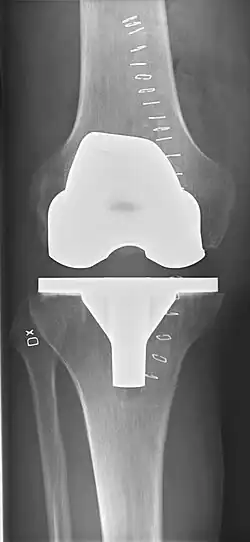

Knee replacement is routinely evaluated by X-ray, including the following measures:

- FFC: frontal femoral component angle. It is typically regarded as optimal when being 2–7° in valgus.[67]

- FTC: frontal tibial component angle, which is regarded as optimal when being at a right angle. A varus position of more than 3° has generally been found to increase the failure rate of the prosthesis.[67]

- Anterior femoral notching (the femoral component causing reduced thickness of the distal femur anteriorly), seems to cause an increased risk of fractures when exceeding about 3 mm.[68]

- LTC: lateral (or sagittal) tibial component angle, which is ideally positioned so that the tibia is 0–7° flexed compared to at a right angle with the tibial plate.[67]